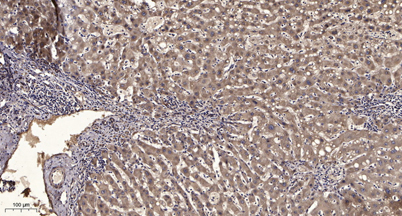

Dilutions: WB 1:500-2000;IHC-p 1:50-300; ELISA 2000-20000

Immunogen: The antiserum was produced against synthesized peptide derived from human SHP-1 around the phosphorylation site of Tyr564. AA range:530-579